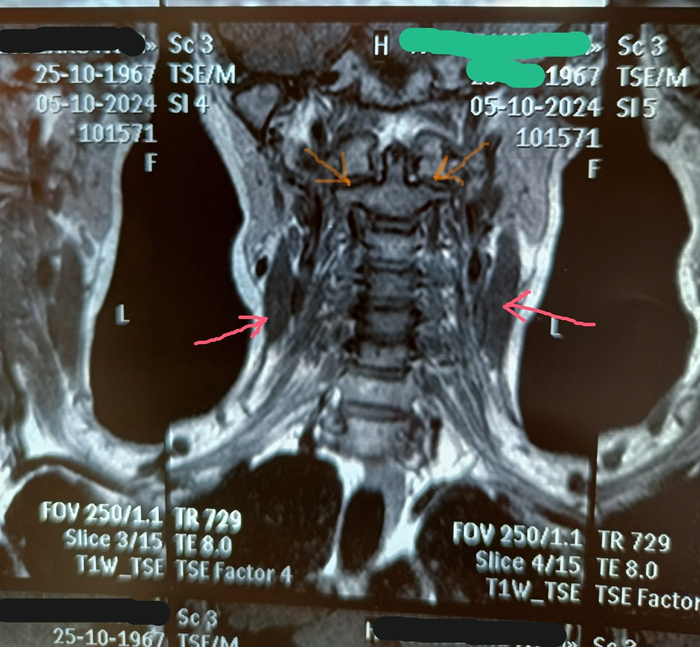

Итак, клинический случай: последствия неправильного лечения болей в спине.

Пациент мужского пола, 42 года, обратился с жалобами на хроническую боль в пояснице, онемение левой ноги и слабость в стопе. Симптомы прогрессировали в течение 8 (!) лет. При осмотре выявлено снижение сухожильных рефлексов на левой ноге, гипотрофия мышц голени, положительный симптом Ласега, оценка боли по ВАШ 7 из 10, сильная хромота.

Анамнез:

В 2017 году пациент впервые почувствовал умеренную боль в пояснице после физической нагрузки. Вместо обращения к неврологу он начал посещать массажиста, который диагностировал «мышечные зажимы» и применял агрессивные техники глубокого разминания. После каждого сеанса онемение в ноге усиливалось (это ключевой флаг, если бы стало легче, то и ладно, неспецифическая мышечная боль, массаж провели, мышцы отпустило, живем дальше), но массажист объяснял это «выходом токсинов и накопившейся психосоматикой». Пациент ходит на массаж с этого времени раз в 4 месяца, отмечая ухудшениие самочувствия с каждым годом.

В октябре 2024 года, после отдыха на море, пациент почувствовал резкое ухудшение из-за резкой боли в пояснице с иррадиацией в левую ногу, боль усиливалась при передвижении, наклонах. В положени лежа появлялось облегчение. Несмотря на это, продолжил самолечение НПВП (кеторолом, нимесилом и уколами диклофенака, да, все вместе, что там с кардиологией и печенью - вопрос отдельный, посещение кардиолога и гепатолога настоятельно рекомендовано) и постельным режимом, избегая визита к врачу. К 2025 году развилась стойкая слабость в левой стопе: пациент начал подволакивать ногу при ходьбе.

Обследование:

МРТ поясничного отдела показала секвестрированную грыжу диска L4-L5, сдавление нервного корешка L5, признаки миелопатии, спондилодисцит. Мышечная гипотрофия свидетельствовала о длительной денервации.

Проведена терапия глюкокортикостероидами, параентерально назначены нейропротекторы, но прогноз восстановления функций ноги — неблагоприятный. Требуется хирургическое вмешательство (пациент на лечении в нейрохирургии и я его потерял на данный момент из виду).

Анализ случая:

Изначально небольшая, веротяно, экструзия диска трансформировалась в секвестрированную грыжу из-за упущенного времени и отсутствия лечения при наличии явных красных флагов. Отсутствие коррекции образа жизни и лечения усугубили смещение пульпозного ядра, а длительное сдавление нерва привело к необратимым изменениям. Пациент упустил «терапевтическое окно», когда можно было избежать операции и сохранить качество жизни.

Этот случай — типичный пример осложнений из-за отказа от доказательной медицины в пользу непрофессиональных методов. У 30-40% пациентов с хронической болью в спине в моей практике аналогичный анамнез: попытки лечиться у «мануальщиков», остеопатов или массажистов без должной квалификации приводят к поздней диагностике и необратимым последствиям. Важно информировать пациентов: боль в спине требует сначала исключения серьёзных патологий с помощью МРТ/КТ, а не просто «разминаний».